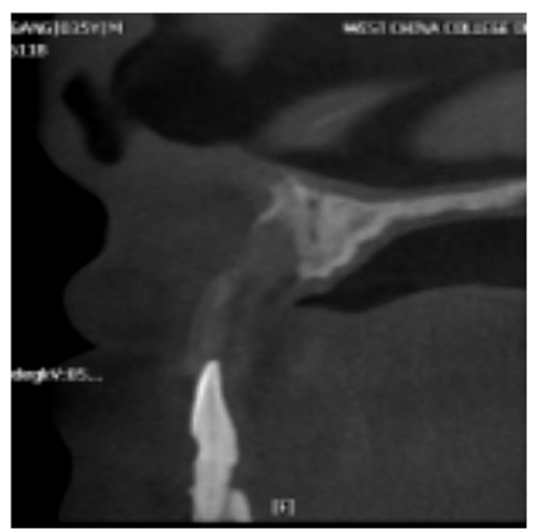

图21 术前CBCT片矢状位

显示在上颌前牙区的牙槽骨高度明显不足

图22 术后CBCT片矢状位

显示植骨后种植体植入,唇侧有明显植入骨影像

图23 植骨术后CBCT片矢状位

显示在上颌前牙区的牙槽骨植骨术后的一个层面

图24 植骨术后CBCT片冠状位

显示在上颌前牙区牙槽骨植骨术后,高密度影为固定骨块的螺钉

图25 植骨术后CBCT片水平位